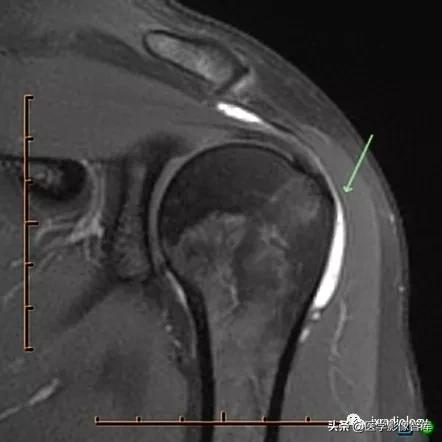

图1:肩峰下 - 三角肌下滑囊(subacromial-subdeltoid bursa)